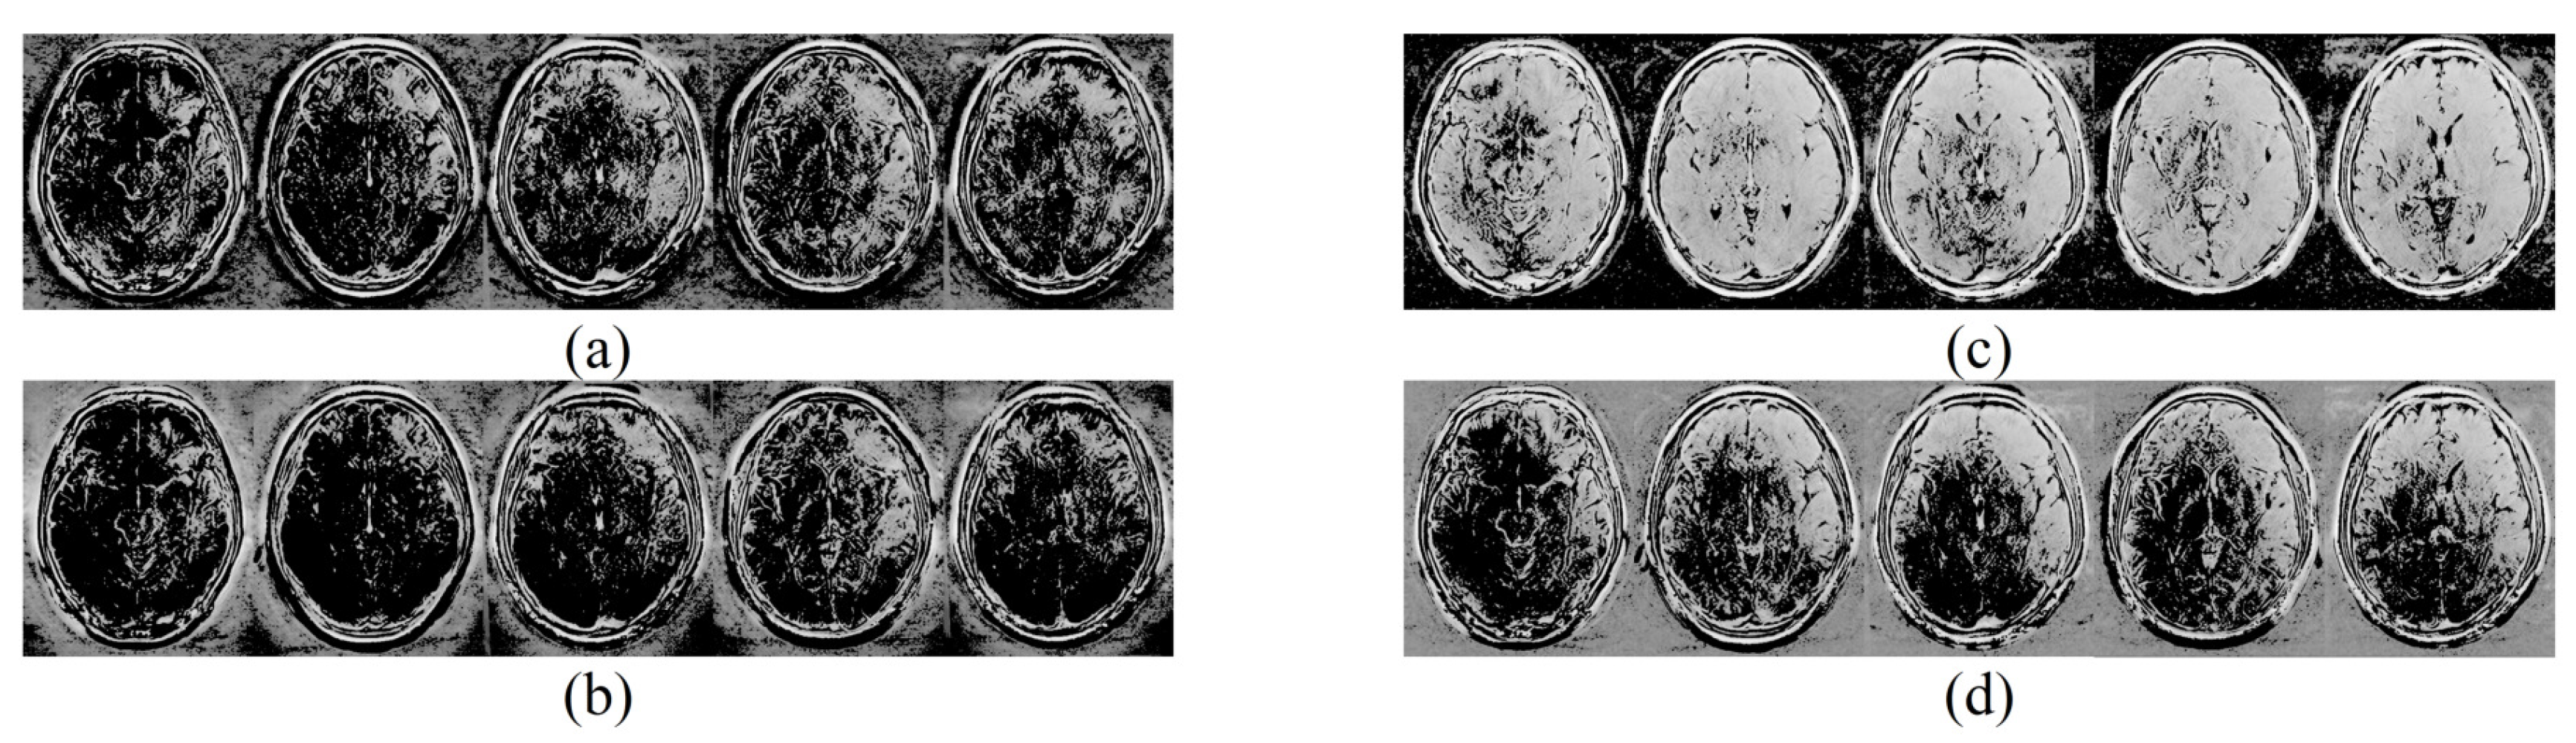

4.1. The Resolution Preservation Ability Enhancement Brought by the Optimizations on Methodology

4.2. Other Visual and Numerical Comparison with the Previous Methods